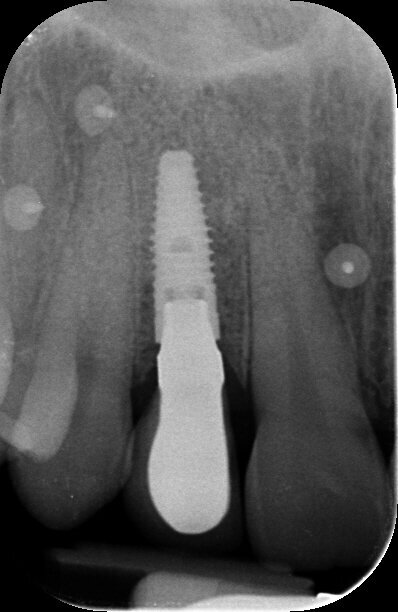

Gli esami radiografici completano l’approccio diagnostico iniziale e lo studio delle radiografie endorali del gruppo frontale, di un’ortopantomografia delle arcate dentarie e di una CBCT permettono di evidenziare un corretto allineamento radicolare degli elementi dentari contigui all’edentulia da trattare e una moderata atrofia orizzontale della cresta alveolare edentula (Fig. 1). Trattandosi di una riabilitazione del settore frontale è opportuno realizzare una dettagliata analisi estetica supportata da un esame fotografico corredato di fotografie extraorali (del volto e del sorriso), fotografie intraorali e da una ceratura diagnostica. L’attenzione iniziale è rivolta principalmente all’analisi dei tessuti molli e degli elementi dentari; in particolare, nel caso descritto, la paziente non presenta fattori estetici sfavorevoli dal momento che si riscontra la presenza di una linea del sorriso media, elementi dentari in area estetica sani e non discromici, fenotipo gengivale spesso, simmetria della festonatura gengivale e buona rappresentazione delle papille interdentali. Osservando in visione frontale la situazione clinica iniziale si evidenzia una lieve recidiva ortodontica dell’elemento 1.1 che si presenta leggermente mesializzato e vestibolarizzato rispetto alla sua posizione ideale (Fig. 2).

Fig. 1 - CBCT della situazione clinica iniziale.